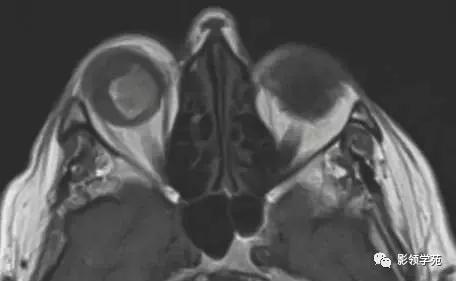

图 5 显示右眼球内的转移黑色素瘤